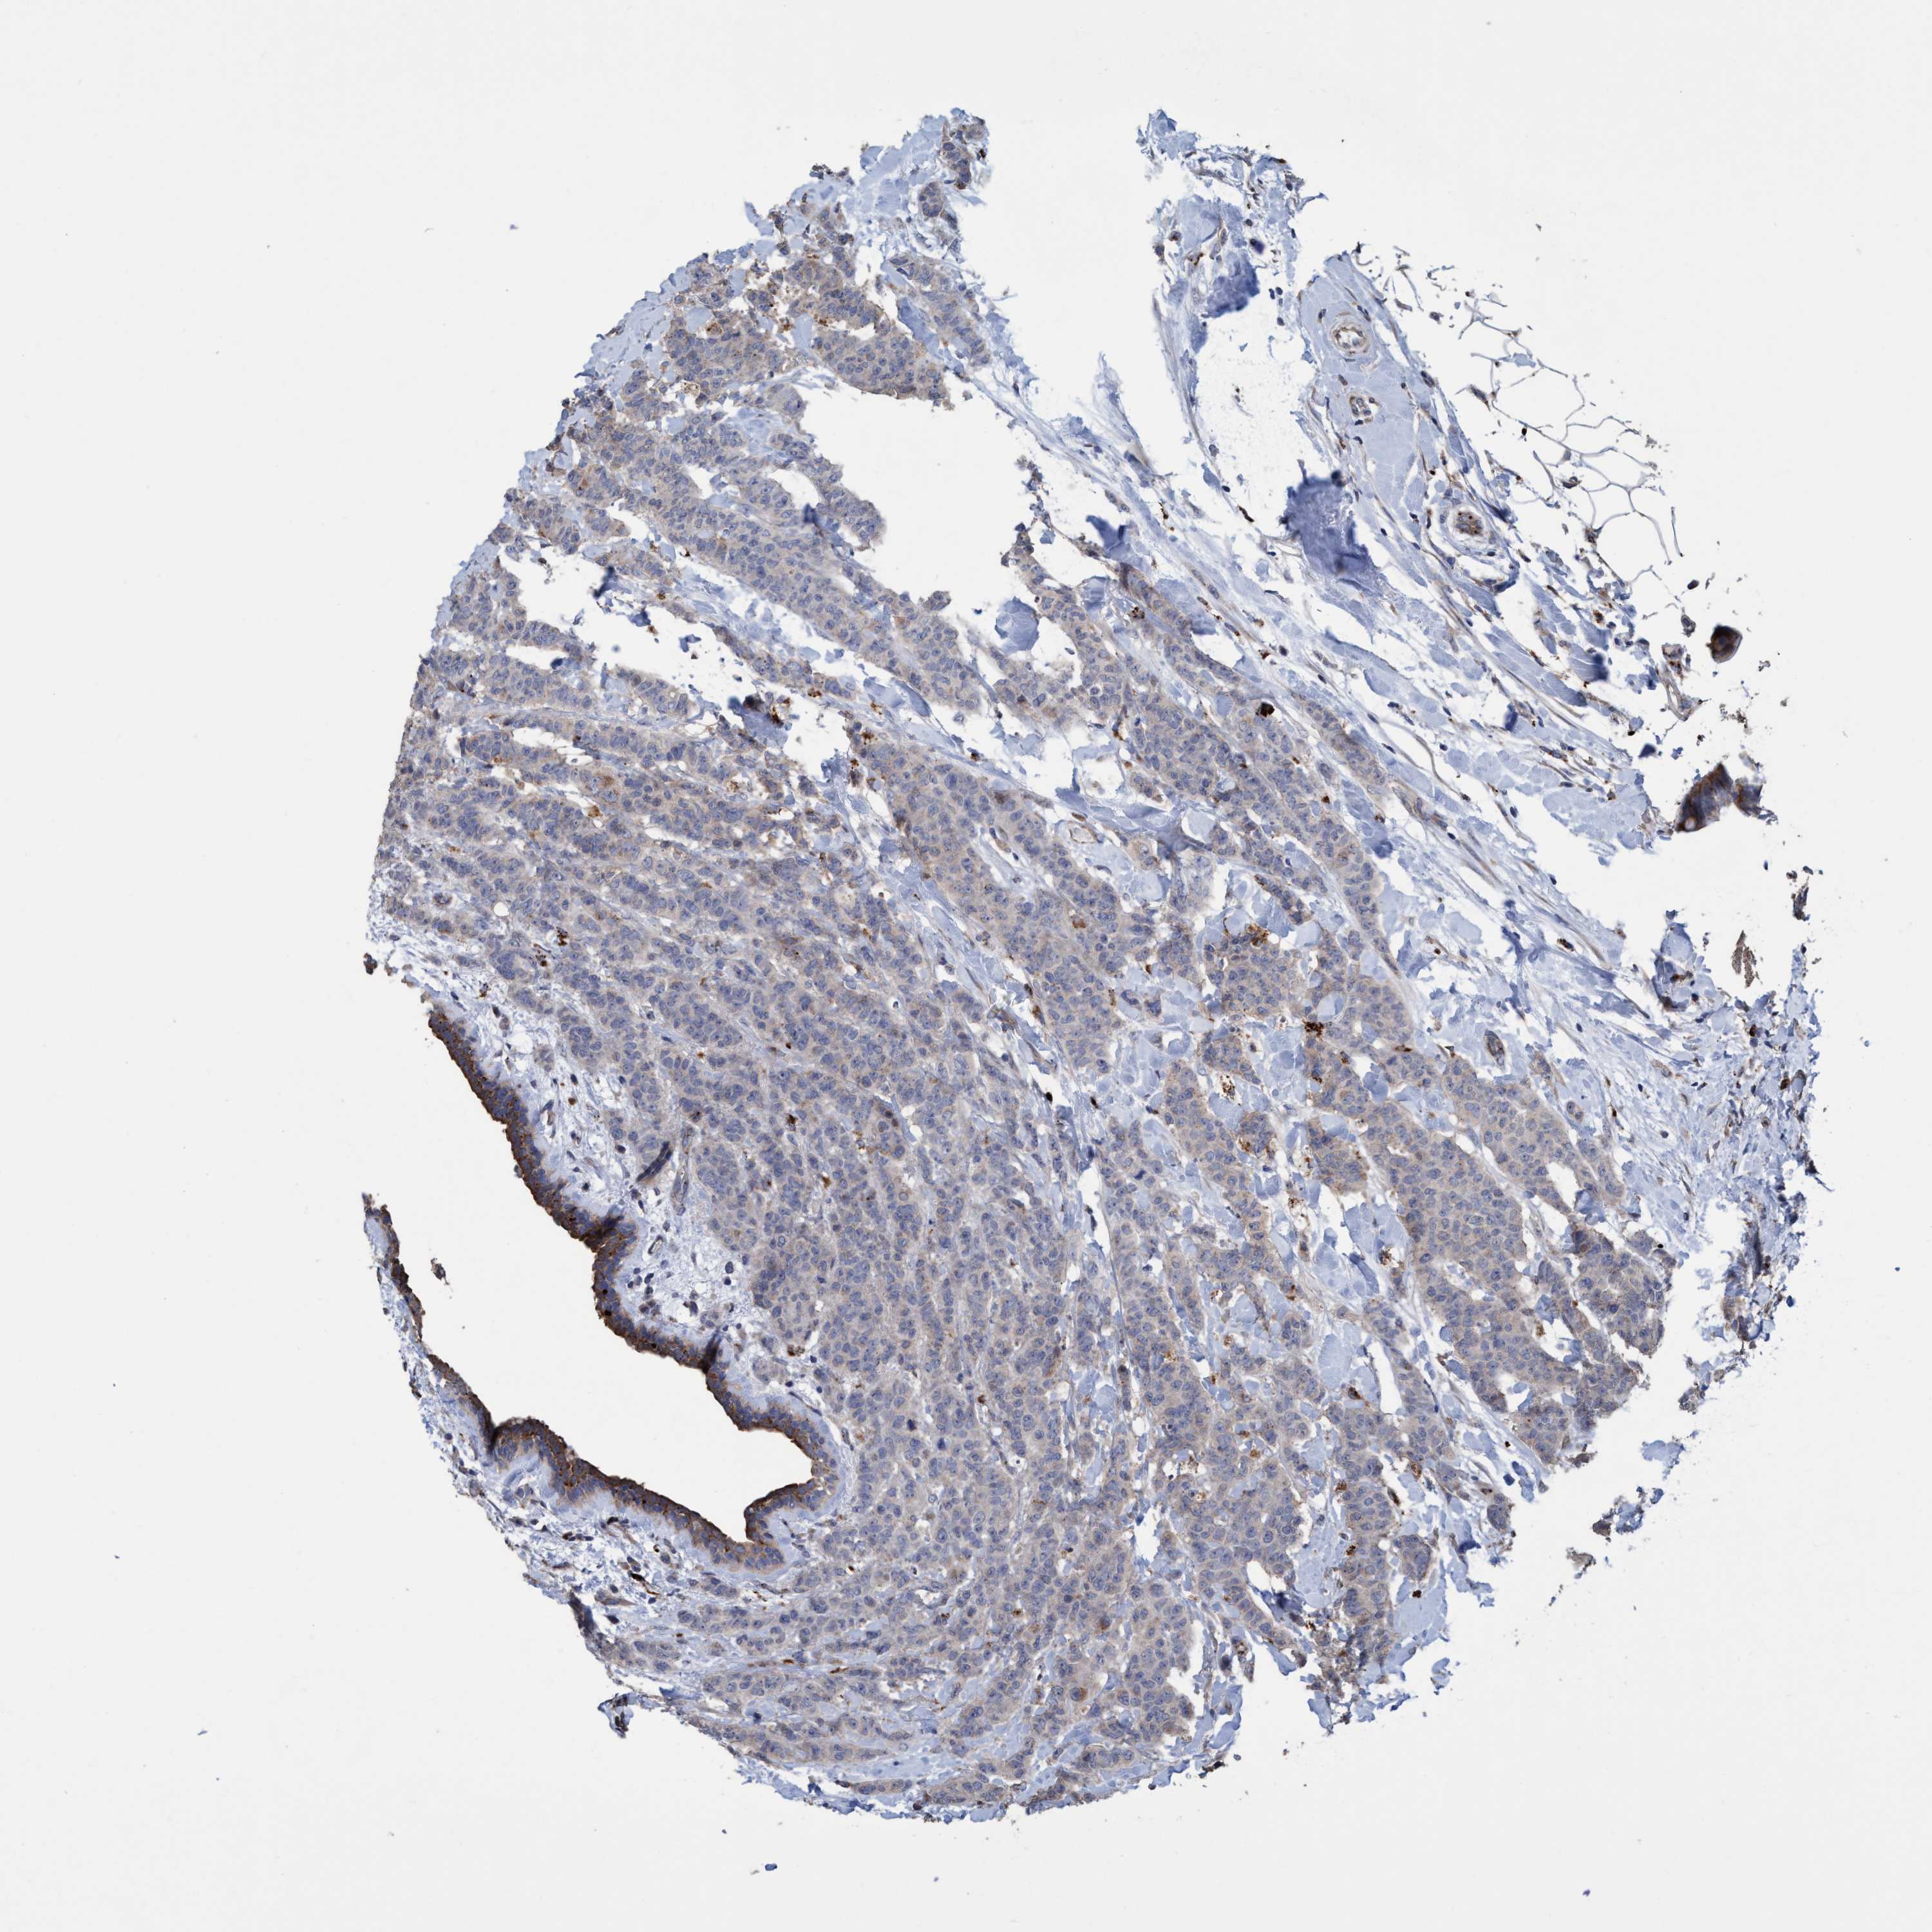

CANCER BREAST CANCER Show tissue menu

BRCA TCGA BRCA VALIDATION PROTEIN EXPRESSION

ANTIBODIES

AND

VALIDATION